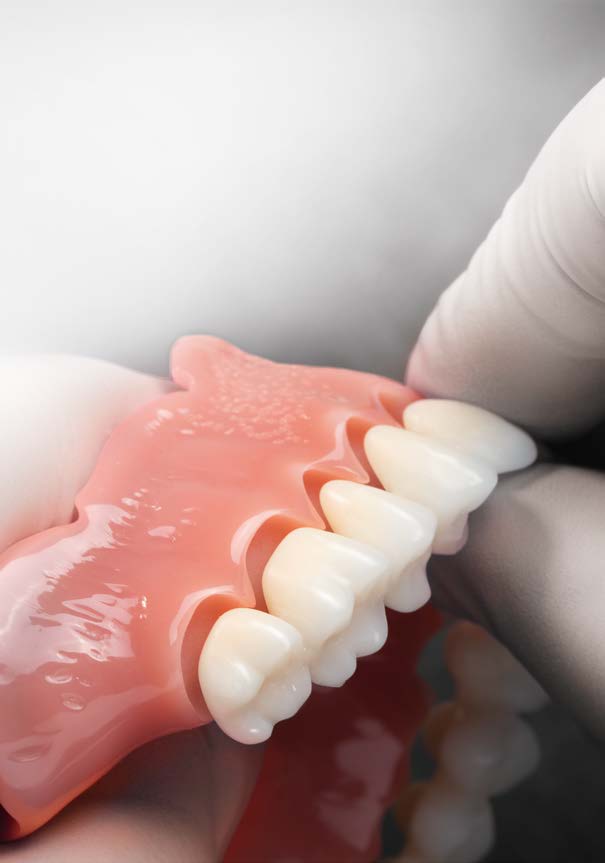

Các Implant ngắn 6.5mm BTI được đặt bằng cách sử dụng quy trình khoan định hướng sinh học (biologically guided drilling protocol) độc quyền của BTI, với lực vặn chèn được đo tại thời điểm đặt để xác nhận sự phù hợp cho việc chịu lực tức thì. Các phục hình tạm thời liên kết bắt vít được gắn ngay sau phẫu thuật để ổn định sự phân bố lực trong quá trình tích hợp xương. Từ 3 đến 6 tháng sau, chúng sẽ được thay thế bằng các cầu răng sứ kim loại cố định hoặc phục hình lai kim loại-nhựa, đảm bảo phục hình hoàn hảo cho bệnh nhân tiêu xương dọc.